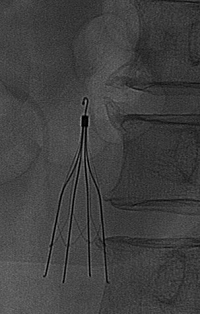

Nephrotic syndrome ȯÀÚ¿¡¼ ESD¸¦ ½ÃÇàÇÑ ÈÄ ¹ß»ýÇÑ pulmonary thromboembolismÀÔ´Ï´Ù. IVC filter¿Í medicationÀ¸·Î È£ÀüµÇ¾ú½À´Ï´Ù.

IVC filter¿Í heparinizationÀ» ½ÃÇàÇÏ¿´°í Á¡Â÷ È£ÀüµÇ¾úÀ½. WarfarinÀ» À¯ÁöÇϱâ·Î ÇÔ.